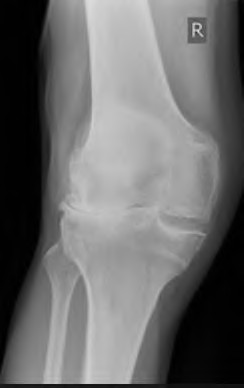

A 55-year-old male presents with isolated medial compartment osteoarthritis of the right knee. He is being evaluated for a medial unicompartmental knee arthroplasty (UKA). Which of the following physical examination or radiographic findings is an absolute contraindication to a medial UKA?

Explanation